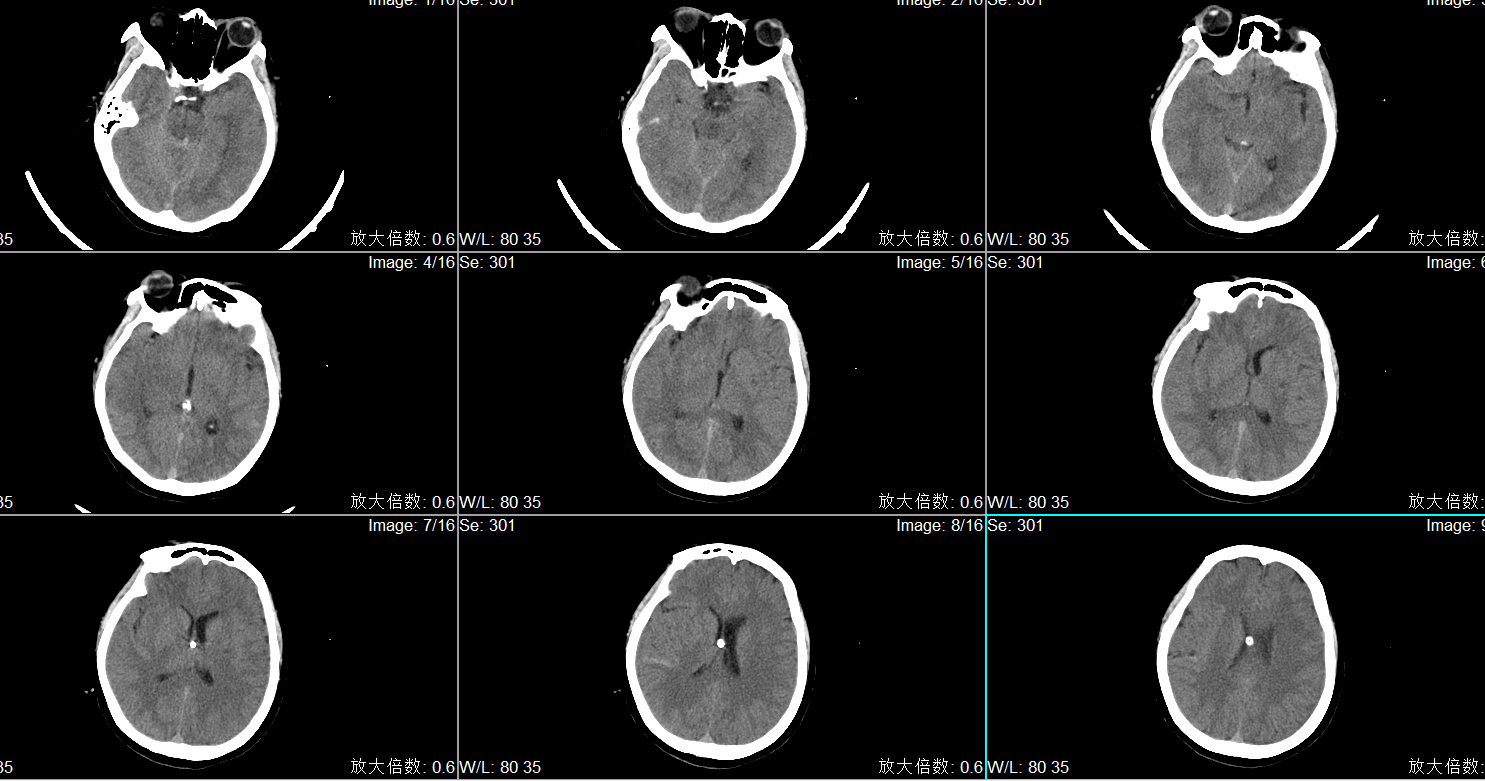

术后头CT